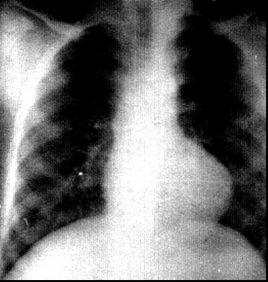

靴形心反映左心排血受阻伴右心室漏斗部發育不全。常見疾病見於主動脈瓣病變、高血壓、冠心病、心肌病或法洛四聯症。

主動脈瓣病變、高血壓、冠心病等所致靴形心病理生理改變以左心負荷增大,左室肥大,向左膨隆,心尖下移。法洛四聯症所致右心室肥大致肺動脈段- 心腰部凹陷, 心尖圓隆, 上翹, 心臟近似靴形 。

肺動脈段凹陷和心尖下移,主動脈結多增寬,形似靴形